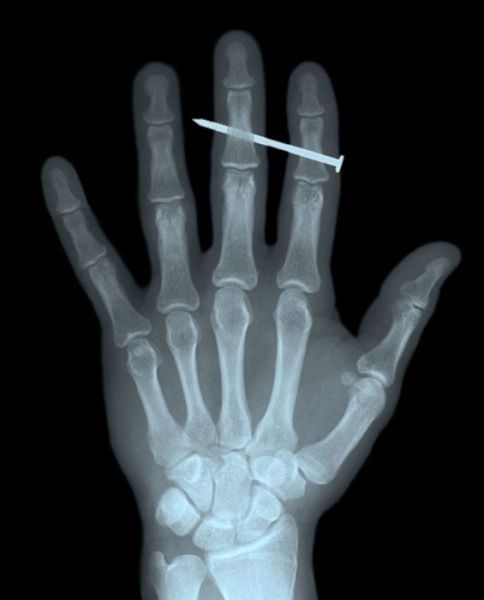

Ковырялся гвоздем в носу?